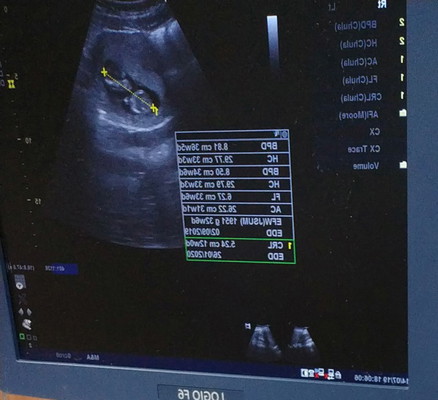

ตอนนี้ตั้งครรภ์12wพอดีคะ จู่ๆมีเลือดออกเป็นสีน้ำตาลๆมา2ครั้ง ตอนเช้ากับตอนเยน..หยดแค่ตอนฉี่คะ ไปหาหมออัลตร้าซาวหมอบอกน้องหัวใจเต้นดีอยู่คะ ให้อนู่ในภาวะแท้งคกคาม..แต่ไม่ได้ให้ยาหรืออะไรมากินเลยแค่ซาวหน้าท้องและช่องคลอดเฉยๆ..ไครเคยเป็นบ้างคะ..หลังจากนั้นจะเป็นอะไรรึป่าว